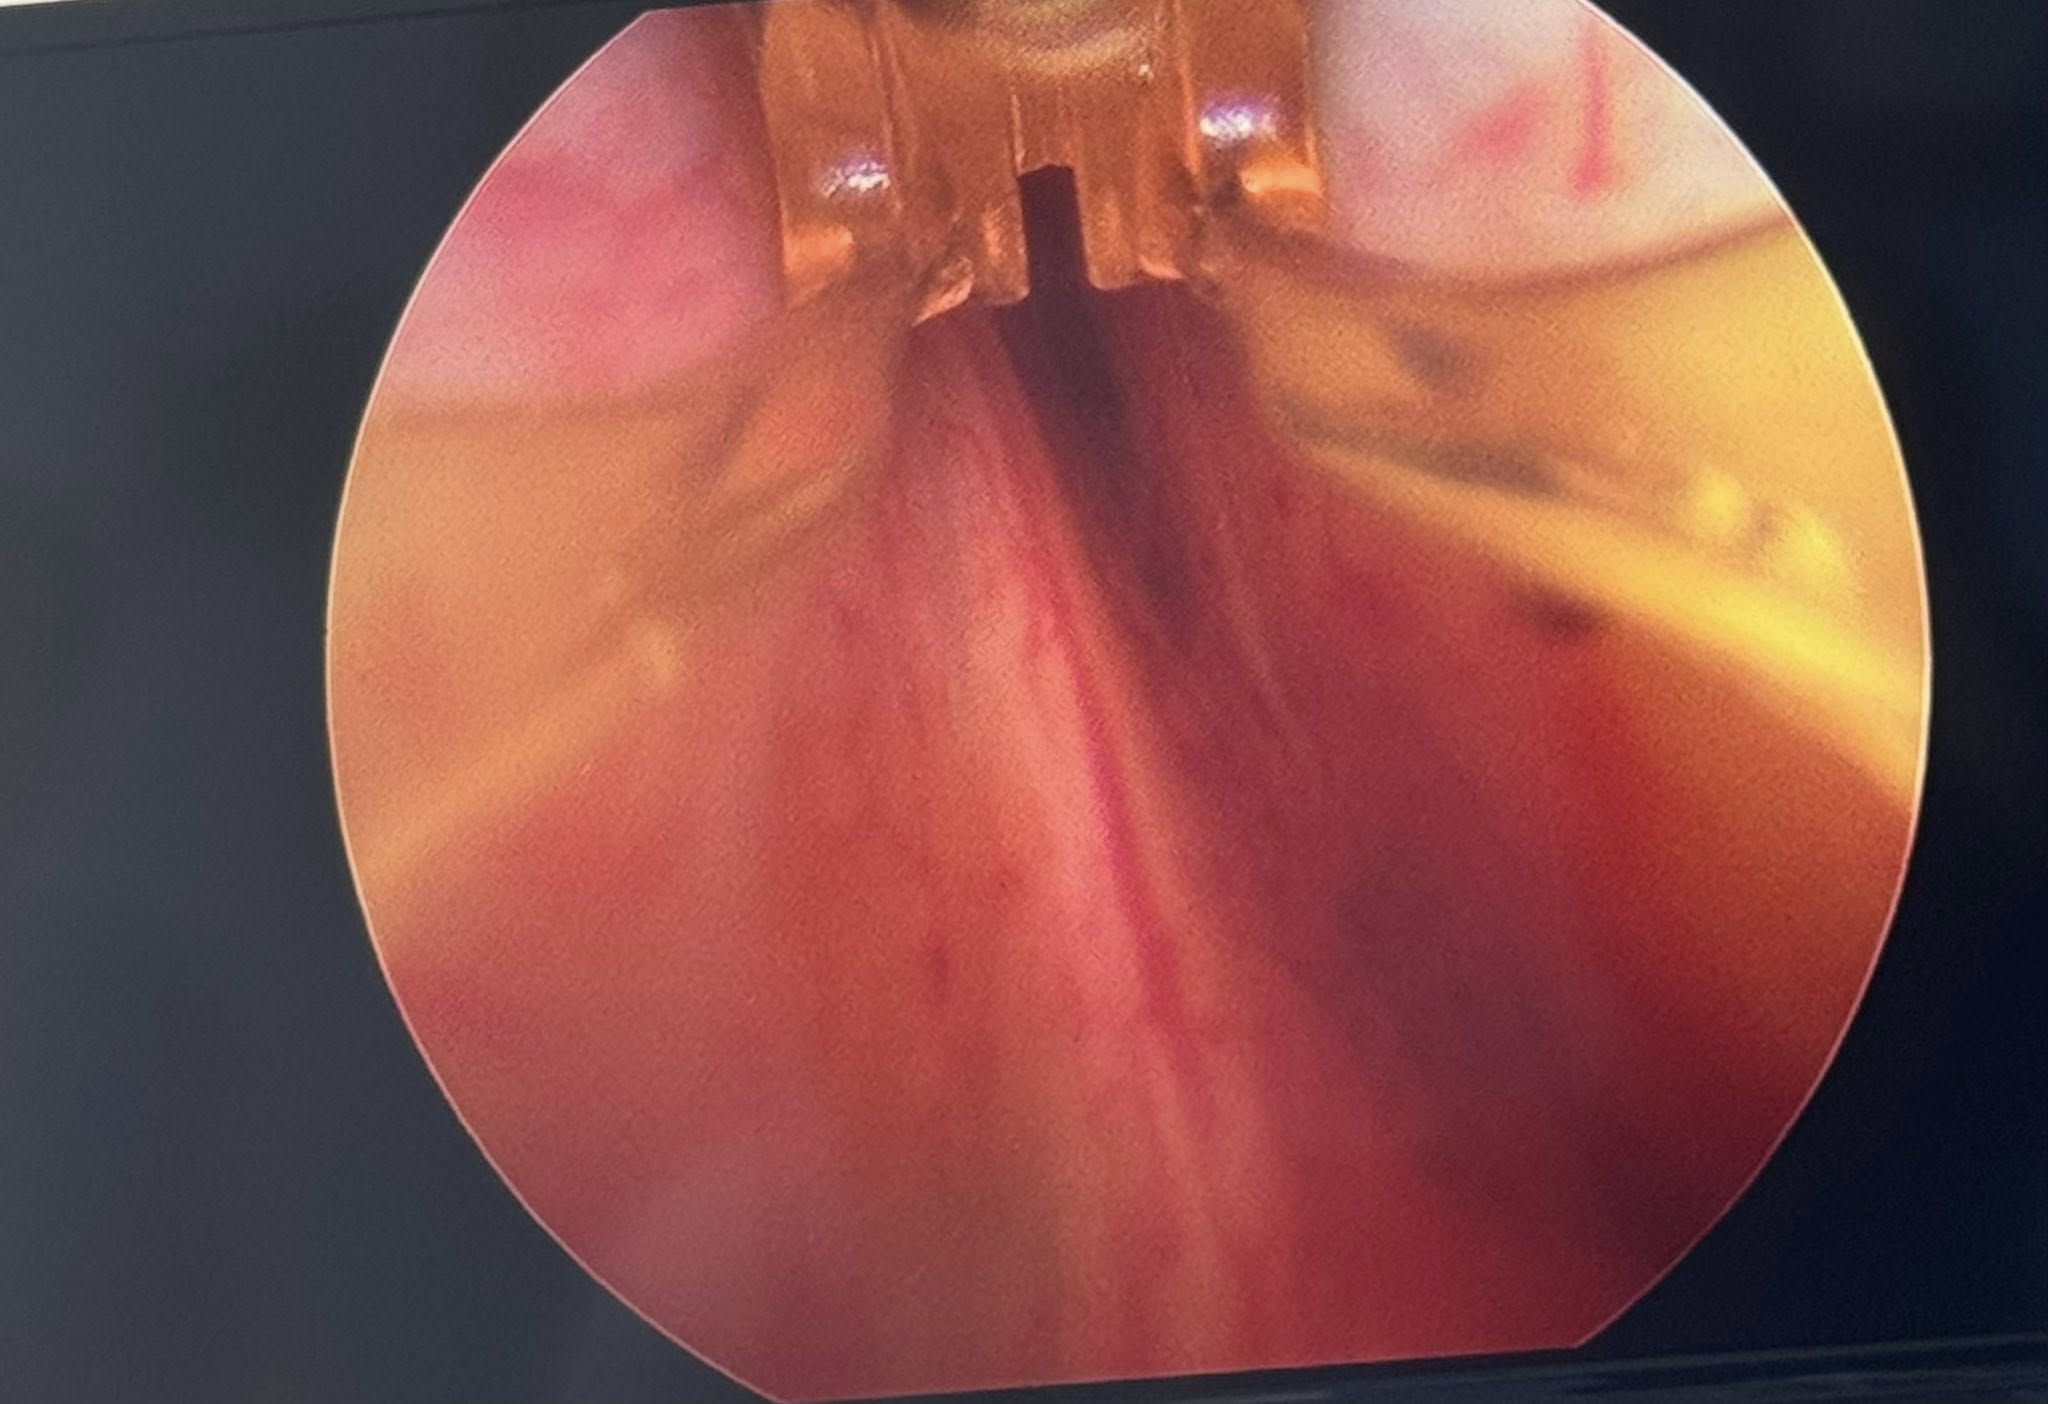

Tratamiento mínimamente invasivo para la hiperplasia prostática benigna (HPB). Reubica el tejido prostático sin necesidad de corte ni resección, aliviando la obstrucción urinaria y preservando la función sexual.

Incluimos imagen comparativa del canal urinario antes y después del procedimiento que muestra la apertura lograda con UroLift.